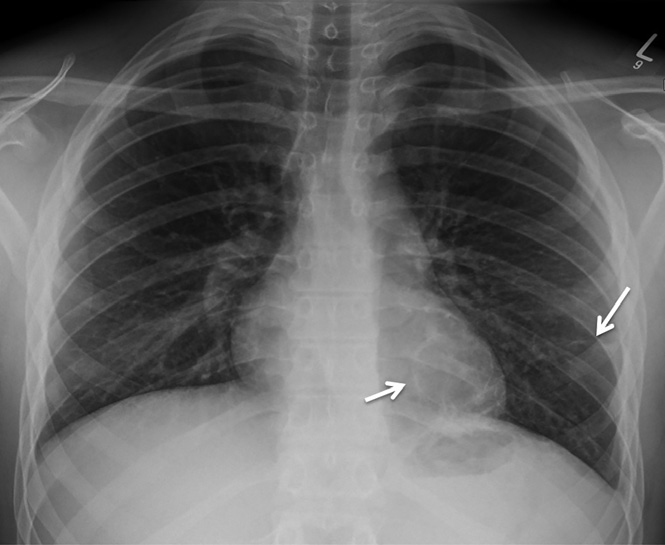

患者支氣管鏡檢查無明顯異常,未見支氣管內(nèi)病變。支氣管肺泡灌洗檢查無抗酸桿菌、細(xì)菌、真菌,分枝桿菌培養(yǎng)物中無病原體生長。患者經(jīng)過14天的哌拉西林/他唑巴坦治療出院。出院8周后復(fù)診,胸部X線顯示實變和氣液平面消退,但左肺下葉發(fā)現(xiàn)兩個殘留的薄壁空洞(圖3)。

圖3 左肺下葉發(fā)現(xiàn)兩個殘留的薄壁空洞(實線箭頭)